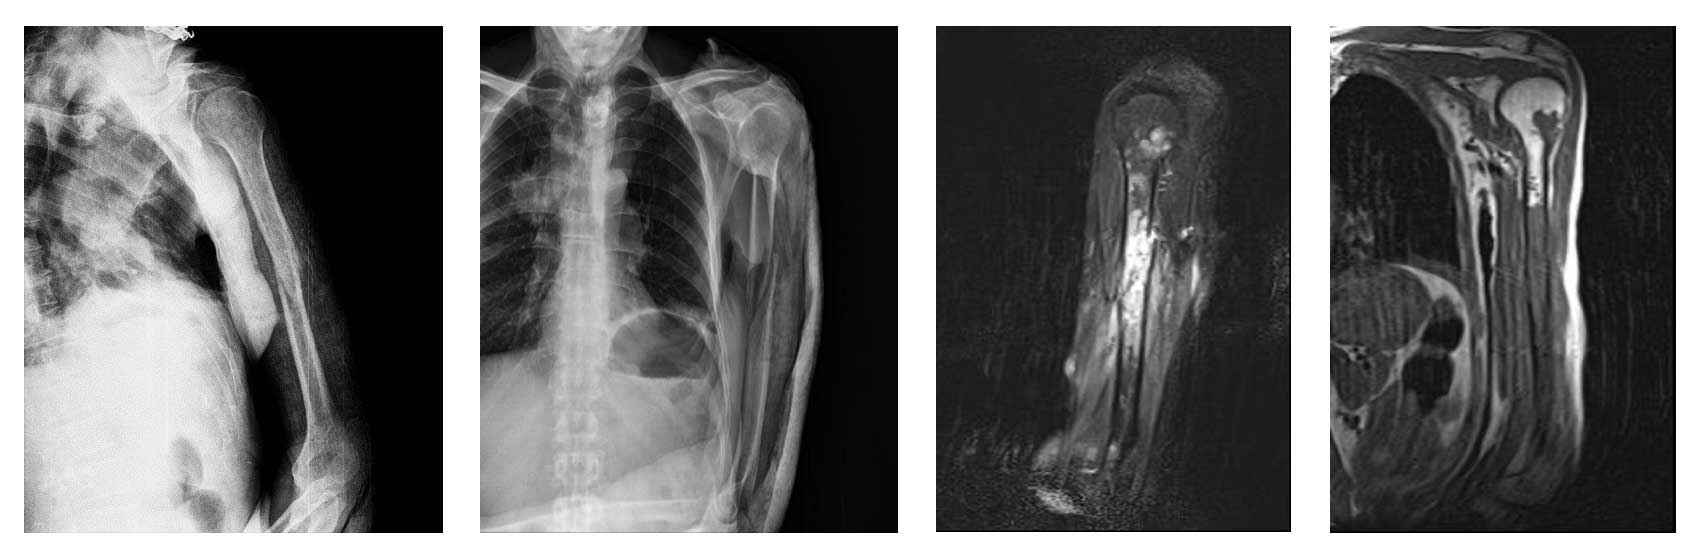

Ameliyat Öncesi: Röntgende sol humerus orta kısımda ayrışmış kırık, MR’da humerus orta kısmı dolduran ayrıca üst kısımda da tutuluma neden metastaz odağı görünmekte.